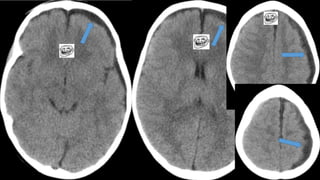

Este documento presenta el caso de un niño de 3 años que sufrió episodios de paresia y alteraciones neurológicas. Exámenes revelaron la presencia de un higroma cerebral que fue drenado. A pesar de una mejoría inicial, el niño continuó presentando síntomas neurológicos intermitentes. Exámenes posteriores identificaron una rara vasculopatía que afecta vasos cerebrales y otros órganos, con un pronóstico grave.